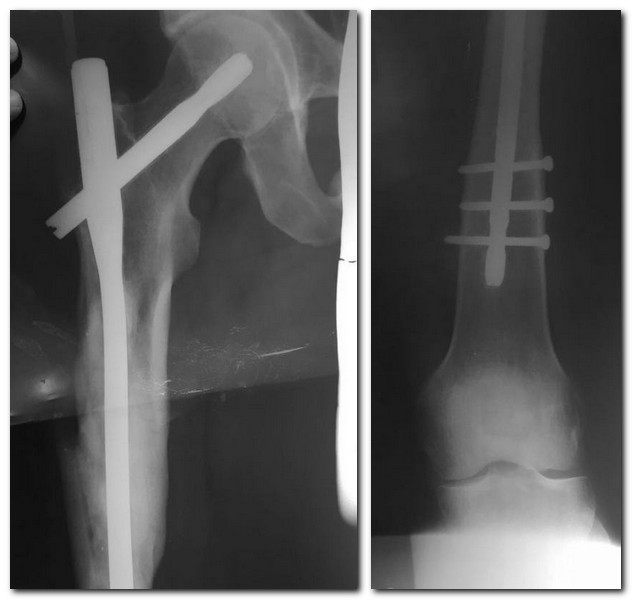

Удаление штифта из бедра

Здравствуйте! Пациент 31 год. Оперирован 3 года назад в другом учреждении. Штифт Санат металл.Особенности удаления, послеоперационного ведения.

Со слов пациента ему штифт мешает. При пальпации умеренная болезненность в области большого вертела, видимо за счёт винта который торчит. Сам пациент очень настаивает на удалении. Попытались отговорить, но настаивает.

Надо бы увидеть хорошие снимки диафиза с областью бывшего перелома, обе проекции. Если есть убежденность, что хорошо срослось - удалять. Особенностей при наличии набора Sanatmetal не вижу.

Как и особенностей послеоперационного ведения.

Если там "песочные часы", и бедро может сломаться после удаления, то лучше пациенту разъяснить, что гвоздь ему протезирует диафиз, и еще на год отложить.Или удалить только винт вверху, или все дистальные.